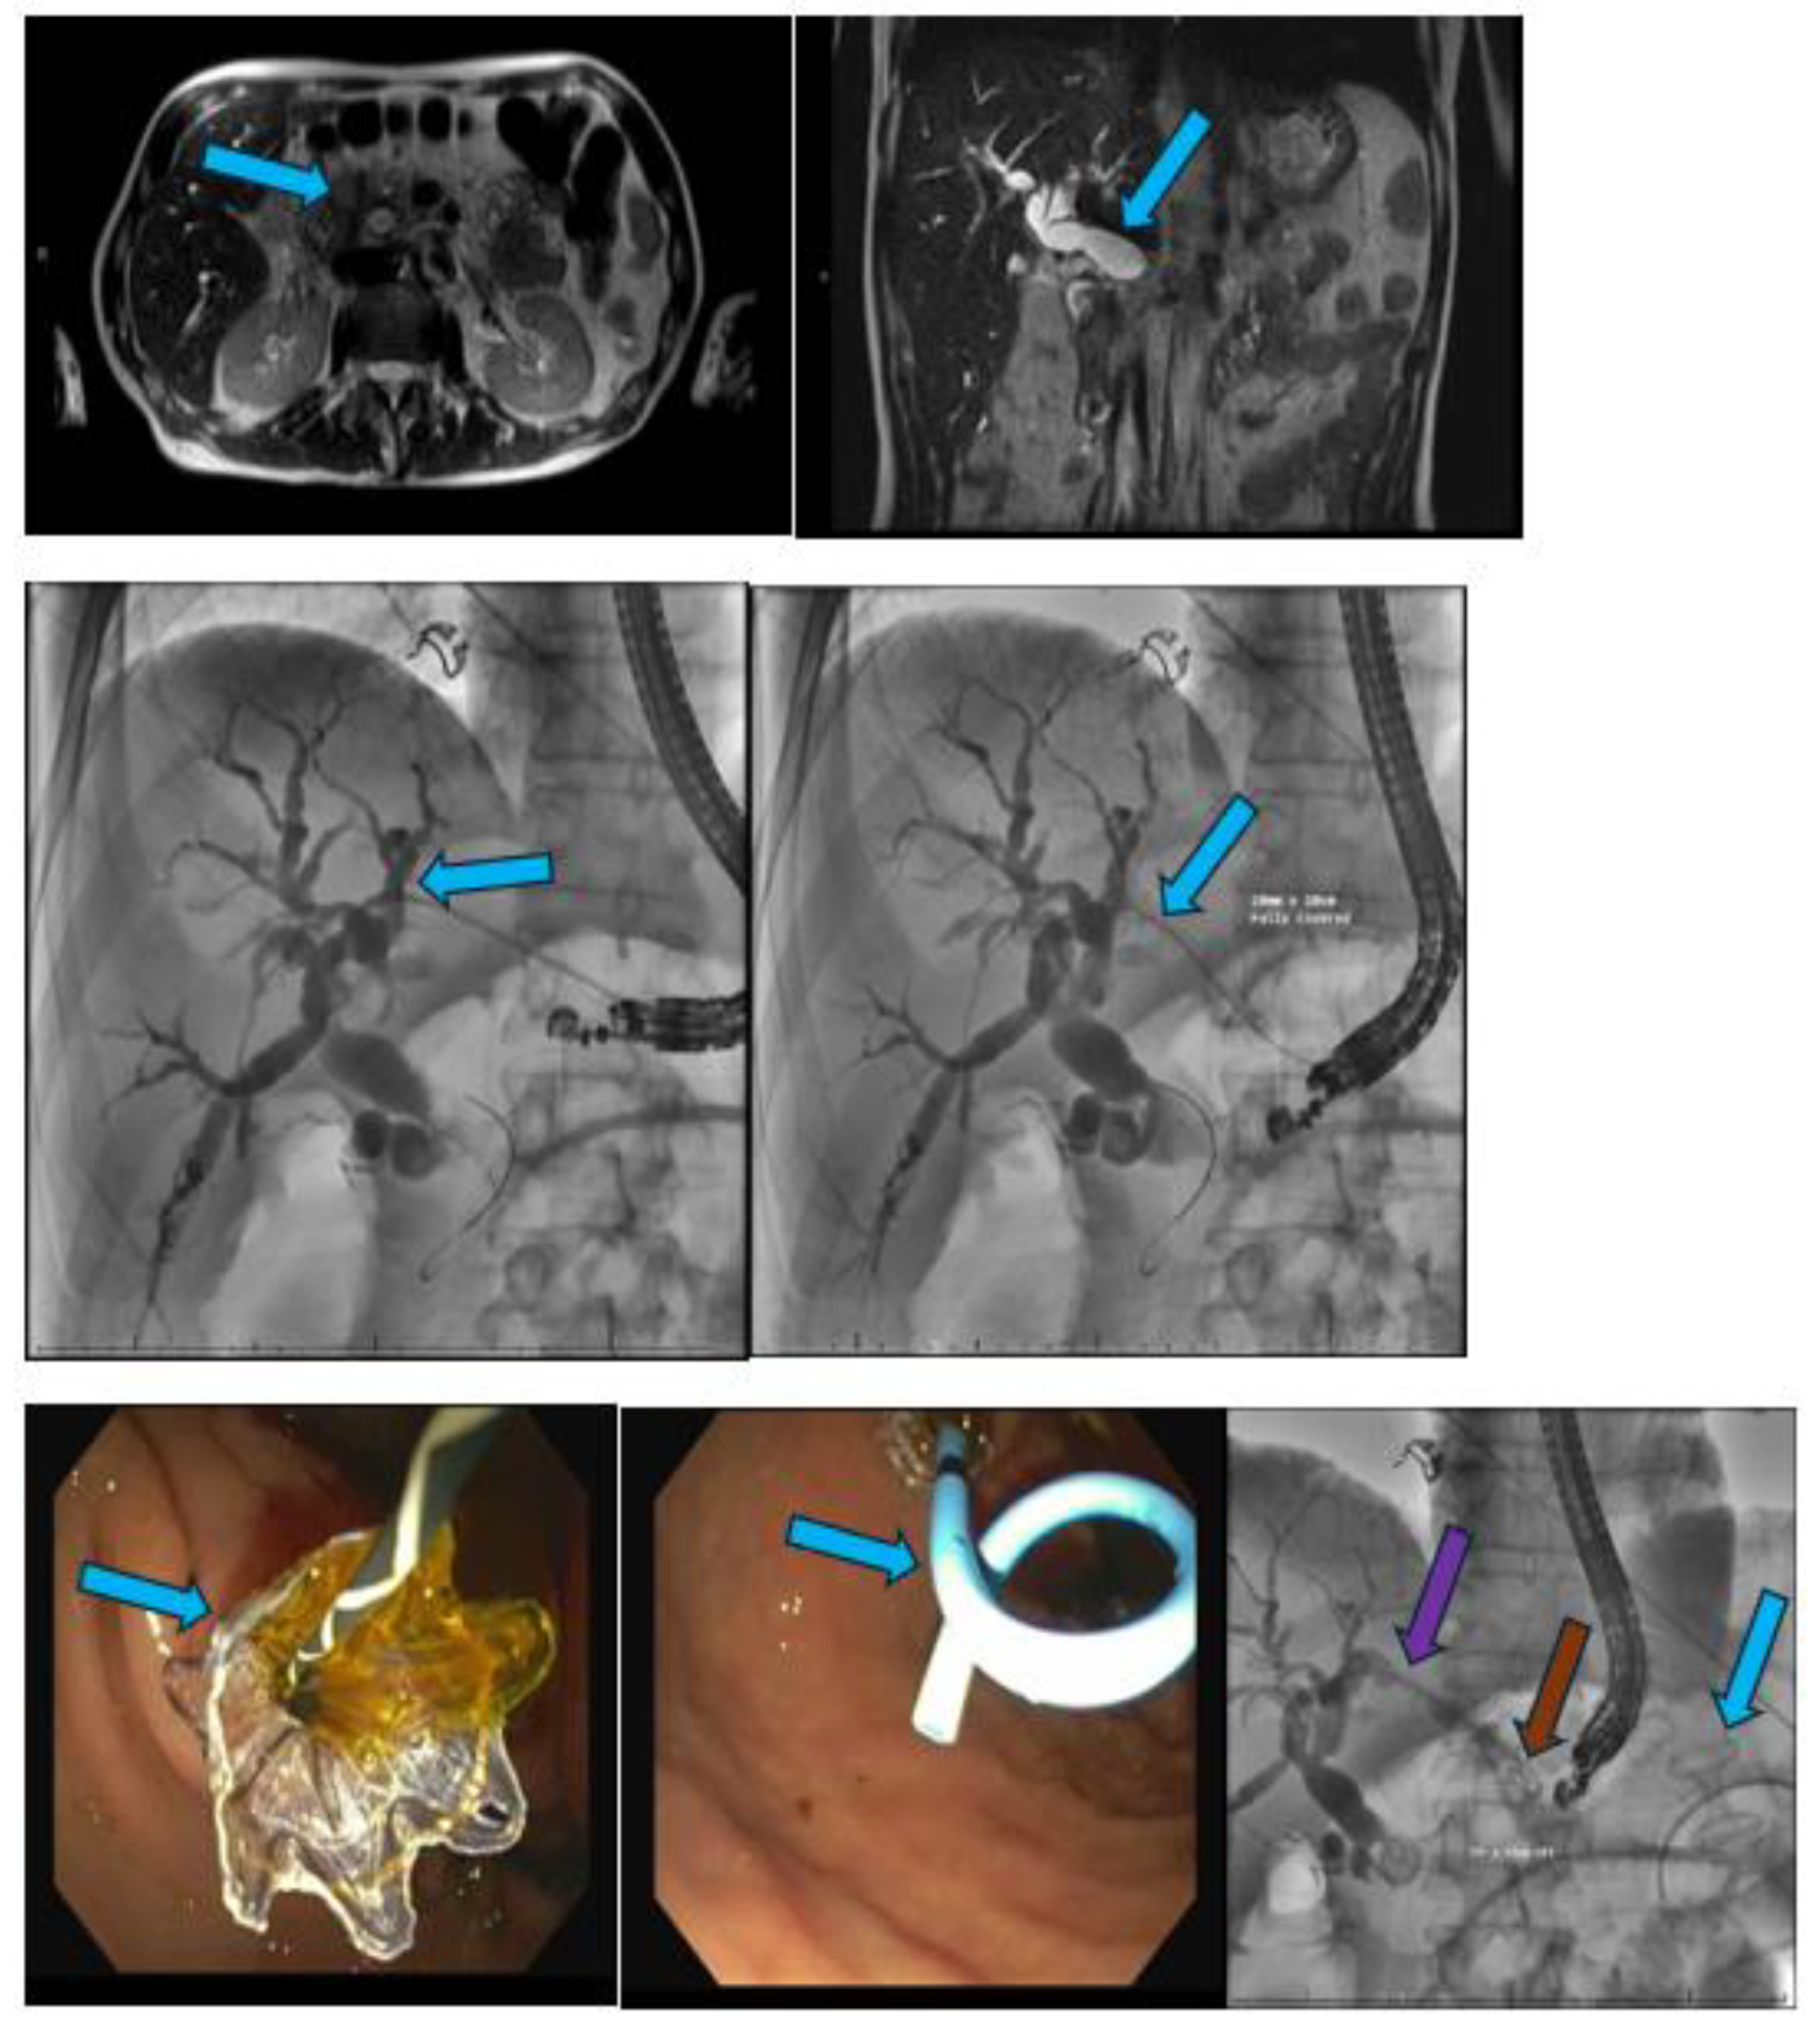

Pancreatic cancer is an aggressive malignancy, and the current 5-year survival rate in the United States, according to the Surveillance, Epidemiology, and End Results Program data, approximates 12%. Although the current standard for resectable pancreatic cancer most commonly includes neoadjuvant chemotherapy prior to a curative resection, surgery in the majority of patients has historically been palliative. The latter interventions include open or laparoscopic bypass of the bile duct or stomach in cases of obstructive jaundice or gastric outlet obstruction, respectively. Non-surgical interventional therapies started with percutaneous transhepatic biliary drainage (PTBD), both as a palliative maneuver in unresectable patients with obstructive jaundice and to improve liver functions in patients in whom surgery was delayed. Likewise, interventional radiologic techniques included placement of plastic and ultimately self-expandable metal stents (SEMS) through PTBD tracts in patients unresectable for cure as well as percutaneous cholecystostomy in patients who developed cholecystitis in the context of malignant obstructive jaundice. Endoscopic retrograde cholangiopancreatography (ERCP) and stent placement (plastic/SEMS) was subsequently used both preoperatively and palliatively, and this was followed by, or undertaken in conjunction with, endoscopic gastro-duodenal SEMS placement for gastric outlet obstruction. Although endoscopic ultrasound (EUS) was initially used to cytologically diagnose and stage pancreatic cancer, early palliation included celiac block or ablation for intractable pain. However, it took the development of lumen-apposing metal stents (LAMS) to facilitate a myriad of palliative procedures: Cholecystoduodenal, choledochoduodenal, gastrohepatic and gastroenteric anastomoses for cholecystitis, obstructive jaundice, and gastric outlet obstruction, respectively. In this review, we synopse these procedures which have variably supplanted surgery for the palliation of pancreatic cancer in this rapidly evolving field.